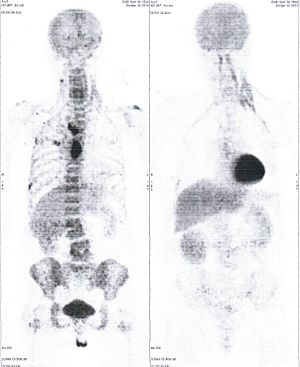

Below are some of the cases, from more than 80 cases we have treated so far with good results. When reading the PET/CT scans, the picture on the left is before treatment, and the picture on the right is after treatment. The intensity of black represents the activity of the cancer, but some black areas are not cancer: brain, heart, radioactive urine in bladder. For the heart, the intensity of black depends on the number of hours of fasting: if more than 10 hours, the heart is not even black, but if fasting is less than 6 hours, it is very black. The intensity of black in the brain can be variable in different scans depending on the brain activity at the time of the scan. The intensity of black in the radioactive urine can also be variable due to the hydration of patients and the time of injection of diuretic.

CASE NO: 35 (SMALL CELL LUNG CANCER)

A 50+ year old man has quite extensive small cell lung cancer on the right side, that has also spread to the liver. This cancer is reputed to be very difficult to treat, and it has failed all cancer treatment. After some treatment, all the cancer in the right lung and liver are gone except for a smaller one remaining in the right lung. Treatment is continuing.